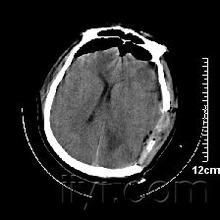

导读: 患者姓名:郭某某 性别:男 年龄:37岁 入院时间:2014年1月6日 病史:因头部坠落伤后昏迷,送院时急诊为重型开放型颅脑损伤,创伤性湿肺,左眼球贯通伤,左声带麻…

导读: 患者郑先生车祸后被紧急送入南京某医院,进行CT及相关影像检查后,发现脑干出血合并脑梗塞,经数次转院及治疗,苏醒后出院,后遗症有:右侧肢体偏瘫,语言、吞咽功能障碍,大…